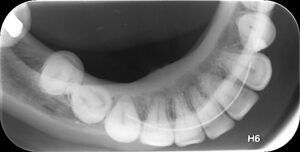

Με την οπισθομυλική ακτινογραφία επιτυγχάνεται η ταυτόχρονη απεικόνιση των μυλών των άνω και κάτω οπισθίων δοντιών ενός ημιμορίου (μιας πλευράς) με μία λήψη. Λαμβάνεται με την τοποθέτηση του ακτινογραφικού πλακιδίου εσωτερικά των δοντιών (προς την πλευρά της γλώσσας και του ουρανίσκου) και παράλληλα με αυτά. Χρησιμοποιείται ειδικός συγκρατητήρας οπισθομυλικών, τον οποίο δαγκώνει ο εξεταζόμενος.

Χρησιμοποιείται για την ανίχνευση τερηδόνων στις μύλες των δοντιών, κυρίως στις όμορες επιφάνειές τους (γειτνιάζουσες επιφάνειες δοντιών).

Η λήψη της είναι γρήγορη (διαρκεί λίγα δευτερόλεπτα) και ανώδυνη.